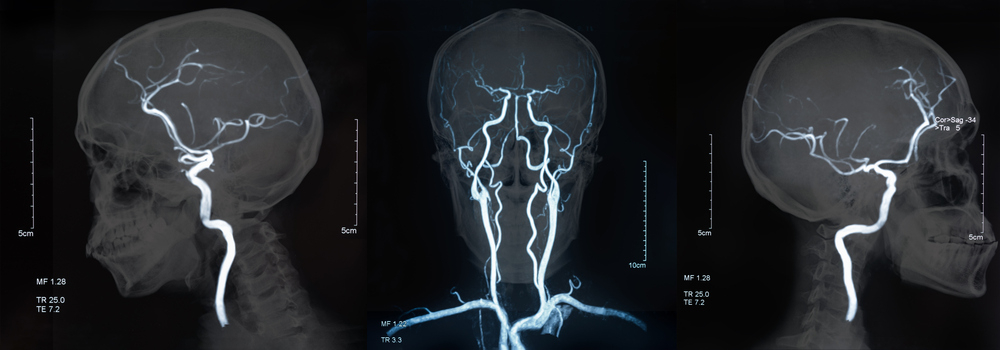

뇌졸중은 뇌혈관의 문제로 갑자기 발생하는 뇌혈관 질환으로, 중증의 응급질환이다. 뇌졸중의 80%는 뇌혈관이 막힌 뇌경색, 나머지 20%는 뇌혈관이 터진 뇌출혈이다. 뇌졸중은 한국인 사망원인 질환 4위이자 성인이 장애를 갖는 원인 질환 1위로, 연간 11만~15만명에게서 새롭게 뇌졸중이 발생한다.

뇌졸중은 환자의 생명뿐 아니라 심각한 후유장애를 남길 수 있어 예방과 관리가 필수적이다. 뇌졸중 증상과 초급성기 치료를 기억했다가 증상 발생 시 치료의 골든타임을 지키는 게 중요하다. 세계뇌졸중기구(World Stroke Organization)가 지정한 '세계 뇌졸중의 날(10월29일)'을 기념해 대한뇌졸중학회가 배포한 '뇌졸중 예방과 치료를 위한 5가지 실천 사항'을 알아본다.